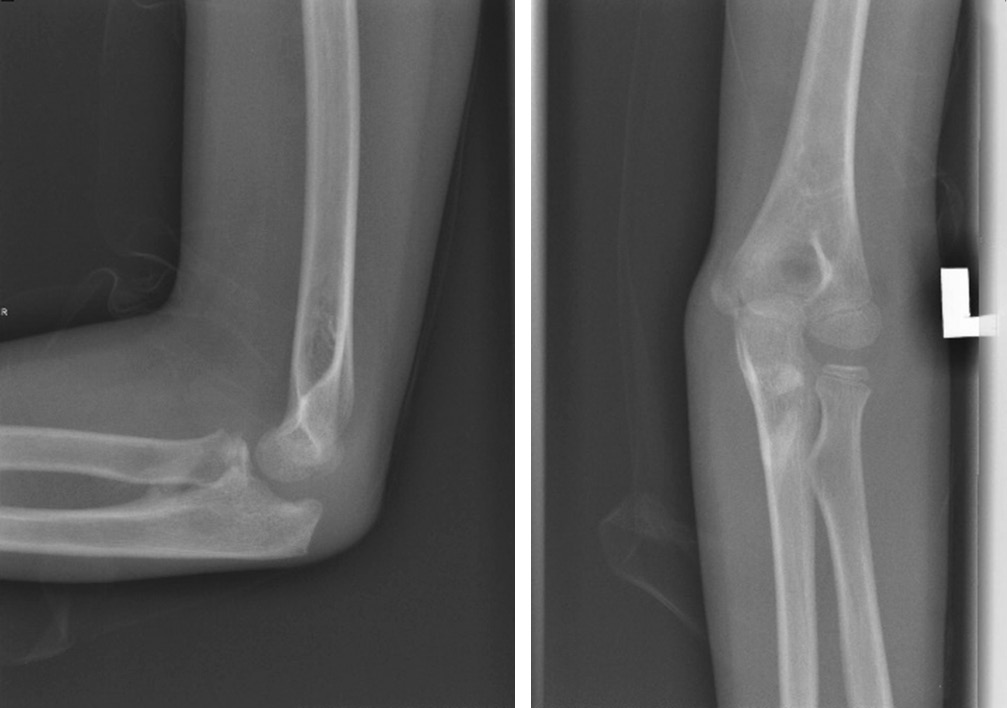

Онемение безымянного пальца и мизинца уменьшилось через неделю после операции. Симптом «когтеобразной кисти» исчез через 2 нед. Перелом зажил, и спицы Киршнера были удалены через 6 нед. (рис. 3). Осторожные пассивные движения в локтевом суставе начаты через 4 нед. с последующим присоединением активных движений через 6 нед. после операции. Лонгета была снята через 6 нед. Через 8 нед. был достигнут полный объем движений в локтевом суставе. Отмечена стабильность локтевого сустава при варусном и вальгусном стресс-тестах. Пациентка смогла вернуться к своей повседневной деятельности, и в данный момент находится под наблюдением с осмотром раз в 3 мес. (рис. 4).

Рис. 3. Перелом сросся через 6 нед. после операции